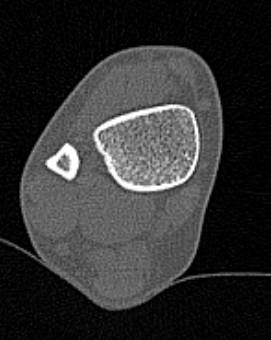

Во время исследования рентгеновская трубка томографа вращается вокруг исследуемой области и производит множество послойных снимков с шагом от 0,5 мм. Полученные снимки поперечного сечения с помощью компьютерной программы могут быть преобразованы в 3D-изображения исследуемого органа. Это позволяет выявлять различные патологические процессы на начальных стадиях и назначать своевременное лечение.

За счет быстроты, доступности и неинвазивности (то есть исследование не требует вмешательства в организм) метод КТ особенно востребован в ортопедии и травматологии. Мультиспиральная КТ лучше всего визуализирует плотные ткани, такие как кости и хрящи. Поэтому, в первую очередь, применяется для диагностики травм суставов (вывихов, подвывихов, переломов).

В отличие от обычного рентгена, при котором изображения костных структур накладываются друг на друга, что затрудняет диагностику, компьютерная томография дает возможность увидеть объемную модель сустава, наглядно оценить пространственное соотношение внутрисуставных структур, суставных поверхностей, расположение костных отломков при переломах и травмах. Это особенно важно в ходе подготовки к оперативному вмешательству и в послеоперационном периоде для оценки успешности проведенной операции.